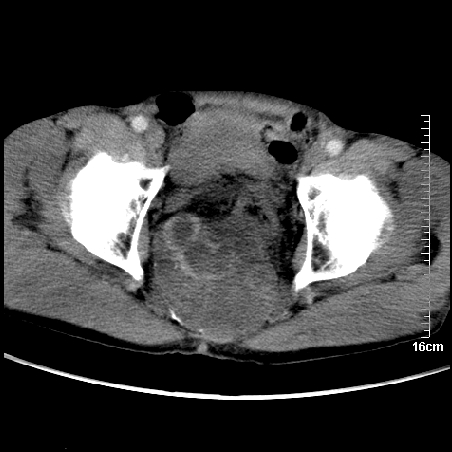

标题: CT16886:骶尾部占位:1.脊索瘤?2.巨细胞瘤? [打印本页]

标题: CT16886:骶尾部占位:1.脊索瘤?2.巨细胞瘤?

增强:

1、骶尾部巨大软组织肿块,部分骶尾骨以被软组织肿块代替,呈不规则侵蚀;病变突向盆腔内;增强扫描病变呈不均质强化;首先考虑脊索瘤。不支持的一点就是病变内无钙化。

2、发生于骶尾椎者须与骨巨细胞瘤鉴别,骨巨细胞瘤一般发在上疗骶椎,肿瘤内无钙化,一般无侵袭性生长的表现。